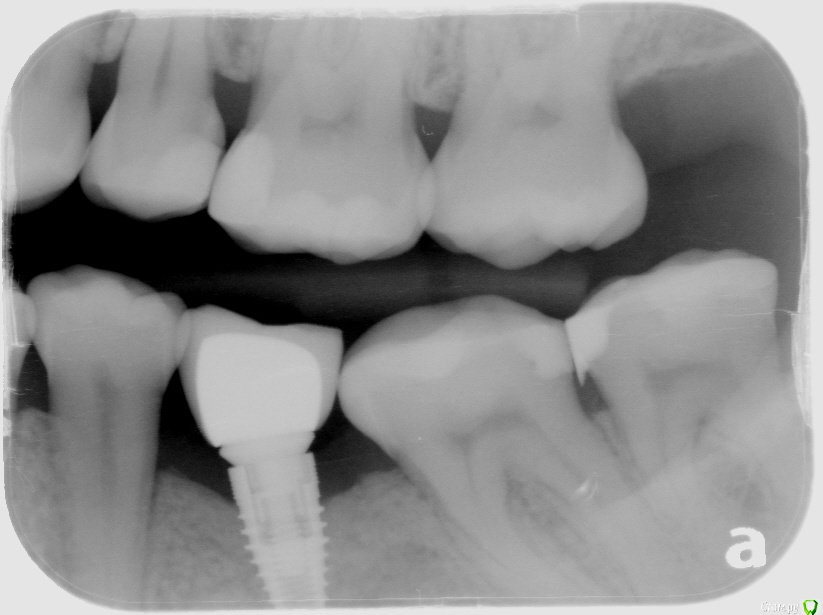

Natalia105 Опубликовано 6 апреля, 2017 Поделиться Опубликовано 6 апреля, 2017 Здравствуйте уважаемые врачи. У меня установлены три импланта в июне 2016 года - на зубы 19, 30 и 31, прижились хорошо. При попытке установки коронок выяснилось, что коронки слишком маленького размера (импланты 30 и 31 стоят слишком близко друг к другу и нет достаточно места чтобы сделать коронки крупнее). Между десной и коронками в глаза бросается металл. Выглядит все это ужасно некрасиво и неестественно. Доктор уверяет меня, что красота в молярах это не главное, а главное это функциональность. Но разве одно с другим несовместимо? Тем более за такие деньги... Да и маленькие коронки тоже ведь снижают функциональность. Коронки сделали только в марте, потому что ждали снятия брекетов. Я пока отказалась от установки таких коронок до выяснения следующих вопросов: 1. Размеры коронок 30 и 31 зубов слишком маленькие, так как недостаточно места. Импланты стоят слишком близко друг к другу, что это - ошибка доктора? Он делал операцию "на глазок" без шаблона (возможно потому, что у меня в тот момент были брекеты). На мои претензии доктор ответил, что кость в том месте мягкая и он не мог поставить 31 имплант дальше. Хотя другой доктор до этого говорил, что с костью у меня там все в порядке (я делала 3D рентген)... Но ведь если кость там действительно мягкая - доктор должен был нарастить ее, не так ли? Потом поставить туда широкий имплант + индивидуальный абатмент, и в итоге коронку нормального размера (это ведь моляр). Так ведь, или я ошибаюсь? 2. В моей ситуации (если не удалять импланты) можно и нужно ли сделать на 31 зуб широкий индивидуальный абатмент и более длинную коронку? При этом с нормальной нагрузкой на имплант (чтобы не расшатался) и чтобы коронка не сломалась под нагрузкой? Или как вариант - одну большую длинную коронку на два импланта? 3. На рентгене видно, что импланты 30 и 31 недостаточно покрыты костью - нужно ли нарастить кость? Или и так сойдет? Если оставить так - не будет ли рецессия кости и не приведет ли в скором времени к потере импланта? 4. Между десной и коронками в глаза бросается металл. Доктор уверял меня, что наращивать десну мне не нужно, потому что там будут скапливаться бактерии (между коронкой и десной), что приведет к воспалению десны и другим неприятным последствиям. Так ли это? Но ведь если десну не нарастить, то на торчащий абатмент будет наматываться еда (особенно мясо) - что тоже неприятно и возможно больно. Да и выглядит неэстэтично... Что же мне делать - наращивать десну или нет? 5. Если оставить 30 и 31 коронки такими маленькими, то имеет ли смысл тогда сделать еще один имплант на 32-й зуб? Во-первых, чтобы продлить зубной ряд - жевательная способность улучшится, во-вторых, нагрузка на 30 и 31 уменьшится (меньше вероятности, что коронка 31-го зуба сломается или расшатается сам имплант 31-го зуба). Ссылка на комментарий

Bier Опубликовано 10 апреля, 2017 Поделиться Опубликовано 10 апреля, 2017 у вас виден край абатмента на котором сидит коронка. По снимкам не очень ясно, можно ли еще спилить 1мм на абатменте, чтобы коронка доходила до десны (разумеется коронку нужно будет новую делать) Ссылка на комментарий